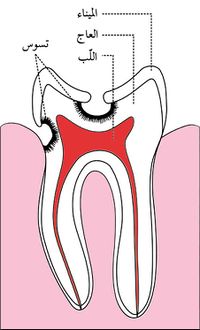

هو تخرب يصيب نسج السن الصلبة بدءاً من طبقة الميناء enamel ثم يصل إلى طبقة العاج محدثاً حفرة قد تزداد اتساعاً وعمقاً لتصل إلى اللب الذي يحتوي الأوعية الدموية والأعصاب.

اللويجة الجرثومية

تتوضع على سطوح الأسنان طبقة عضوية رقيقة تدعى اللويحة الجرثومية bacterial plaque تتألف من طبقات كثيفة ومتراصة من الجراثيم ومنتجاتها والخلايا والبقايا الطعامية، وهي ذات طبيعة سكرية بروتينية لا تنحل باللعاب ولا تزول بغسلها بالماء بل تحتاج إلى فرشاة الأسنان لإزالتها.

تقوم الحموض الناتجة من عملية تخمر السكاكر بحل العناصر المعدنية والعضوية التي تدخل في تركيب ميناء السن فتبدو المنطقة بيضاء طبشورية وذات ملمس خشن. ولدى تزايد إنتاج الحموض وعدم تطبيق الفلوريد الموضعي على الأسنان الذي يقوم عادة بإيقاف تطور التسوس، يتهدم الميناء وتصل الإصابة إلى العاج مشكلة حفرة التسوس التي يمكن ملاحظتها سريرياً ويبدأ الإحساس بالألم لدى التعرض إلى مؤثرات خارجية من سخونة وبرودة أو الضغط أثناء المضغ. عند إهمال معالجة التسوس في هذه المرحلة يزداد التخرب وتصل الإصابة إلى لب السن الذي يصاب بالالتهاب وترافقه موجات حادة من الألم وخاصة في أثناء الليل. إن عدم تطبيق المعالجة الملائمة في هذه المرحلة يؤدي إلى تموت اللب وإصابته بالتعفن وتتكون الخراجات الحادة والمزمنة والآفات الذروية التي تنتهي بقلع السن المصابة.